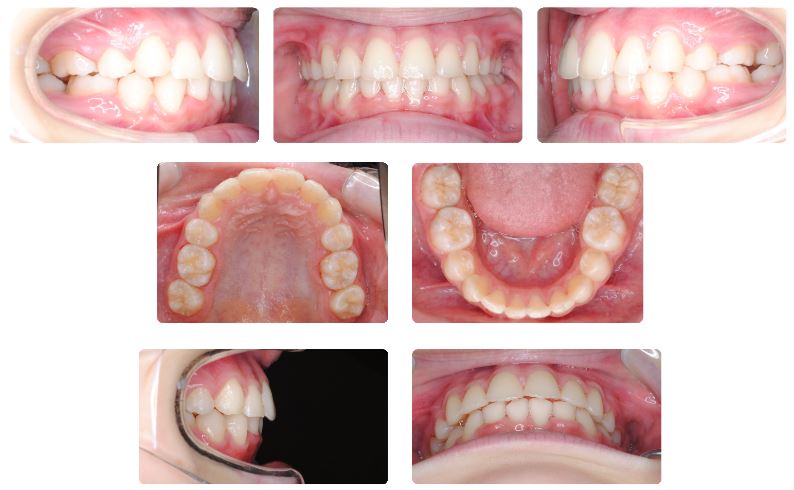

下顎後退を伴う八重歯で噛み合わせの深い症例  10代前半

主訴:八重歯の見た目が気になる

初診時年齢:12歳

性別:女性

診断名:下顎後退をともなう犬歯低位唇側転位

抜歯/非抜歯:抜歯

装置名:マルチブラケット装置

治療費用:約62万円(税抜)と来院時に調節料5,000円(税抜)

治療期間:2年1ヶ月

治療に関する副作用/リスク:歯の移動時の痛み  装置による口腔粘膜の口内炎

前歯の歯並び、特に八重歯が気になるとのことで来院されました。

乳歯が一部残存している時期でしたが、この症例では口元の突出を避けるため上下あごの小臼歯抜歯を選択してワイヤーによる固定式矯正装置で治療を進めました。

治療期間は2年1ヶ月でした。

萌出途中であった上下顎の最後臼歯(第二大臼歯)をしっかり咬ませるのに時間を要しました。